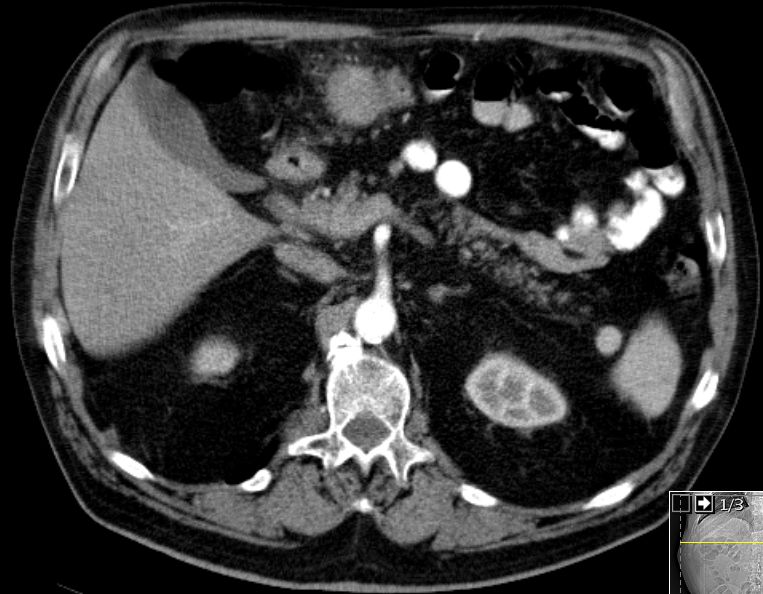

| Colon transversum | 74-jähriger Mann mit einem Colon-Karzinom pT3a pNo(0/17) M1hep L1 V1 G3.![]() |

![]() | ||

![]() |

![]() | |||